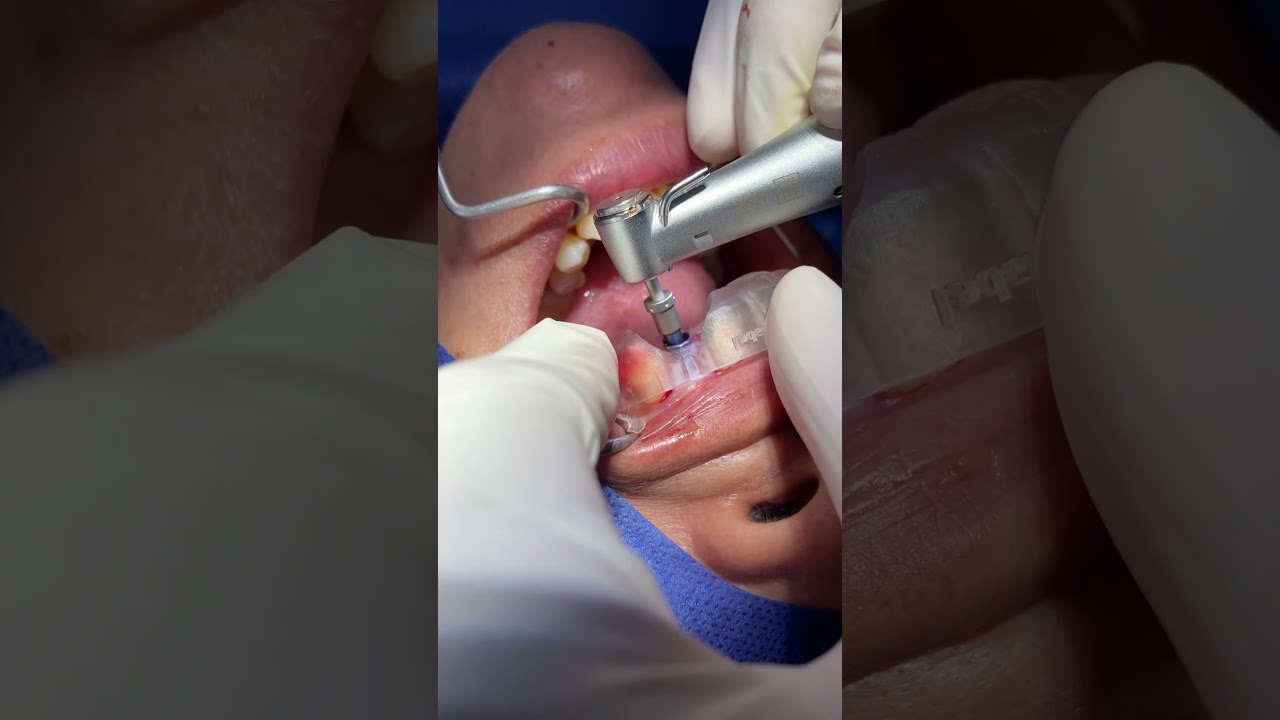

¿Que es un Implante Dental?

- Es un aditamento con forma de tornillo elaborado de titanio o de zirconio, que se inserta en el hueso a través de una pequeña cirugía, hasta que se osteointegre con el hueso y se coloque un provisional y posteriormente una corona definitiva.

-La ventaja de los Implantes Dentales es que sustituyen a los dientes o muelas perdidos sin que se tenga que desgastar los dientes adyacentes para un puente fijo.